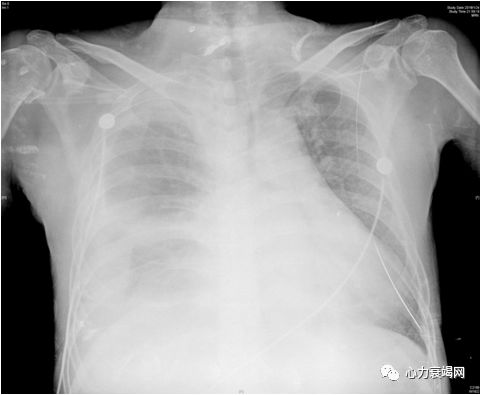

右肺野透过度普遍减低,右肺中下叶膨胀不全,左下肺纹理聚拢; 右侧肋膈角钝,少量胸腔积液; 主动脉结宽; 肺动脉段平直; 左心室增大;

左心功能不全,左下肺及右肺中下叶膨胀不全,右侧胸腔及右侧叶间积液。